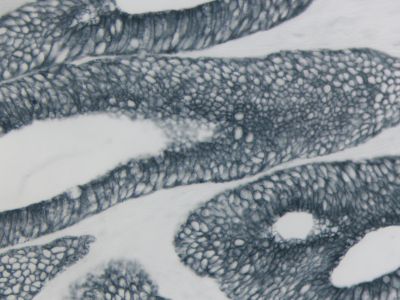

The peroxidase micropolymers of the ImmPRESS HRP polymer reagent limit steric interference and provide enhanced accessibility to the target, avoiding the disadvantages of other polymer systems that use large dextrans or other macromolecules as backbones. The result is crisp, strong staining of antibody targets, especially nuclear and membrane antigens (such as Ki67, estrogen receptor, bcl-2, CD3, CD8 and CD10) and greater sensitivity than other polymer systems.

The staining procedure is simple as shown in the diagram below. Following a blocking step with the diluted normal horse serum, sections are incubated with primary antibody. After a brief wash, the appropriate ImmPRESS Reagent is added to the sections and incubated for 30 minutes. Sections are again rinsed and the slides are developed with the peroxidase substrate of choice.